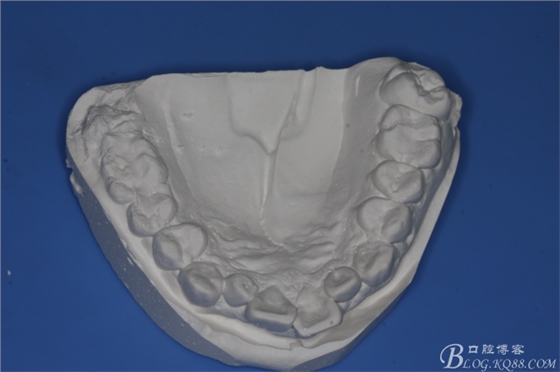

圖1.術(shù)前的正畸科病例:

圖2.術(shù)前的正畸工作模型:47低位近中阻生、37近中中位阻生